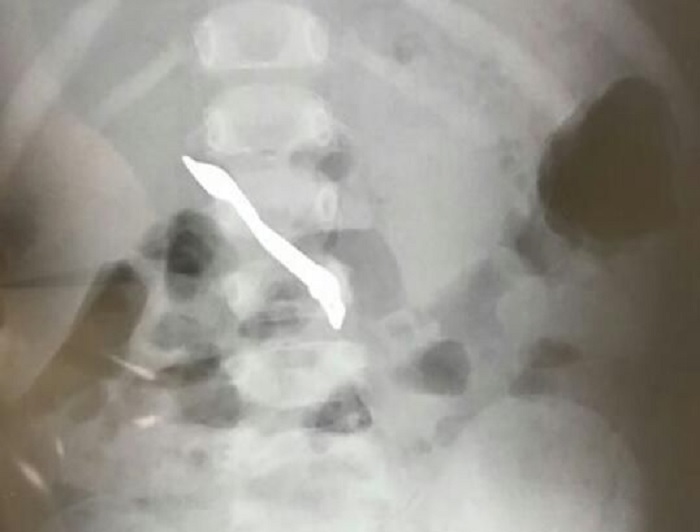

Luego lo trasladaron al Hospital General de Luque, donde tuvo lugar el procedimiento médico que contó con la ayuda del gastroenterólogo norteamericano Bhavesh Shah, voluntario de la Fundación ImaHelps. El adminículo estuvo alojado en su esófago.

«Existía una desproporción importante entre el tamaño del objeto y el esófago. La criatura ya fue trasladado al hospital de origen en buenas condiciones», agregó Luraschi.